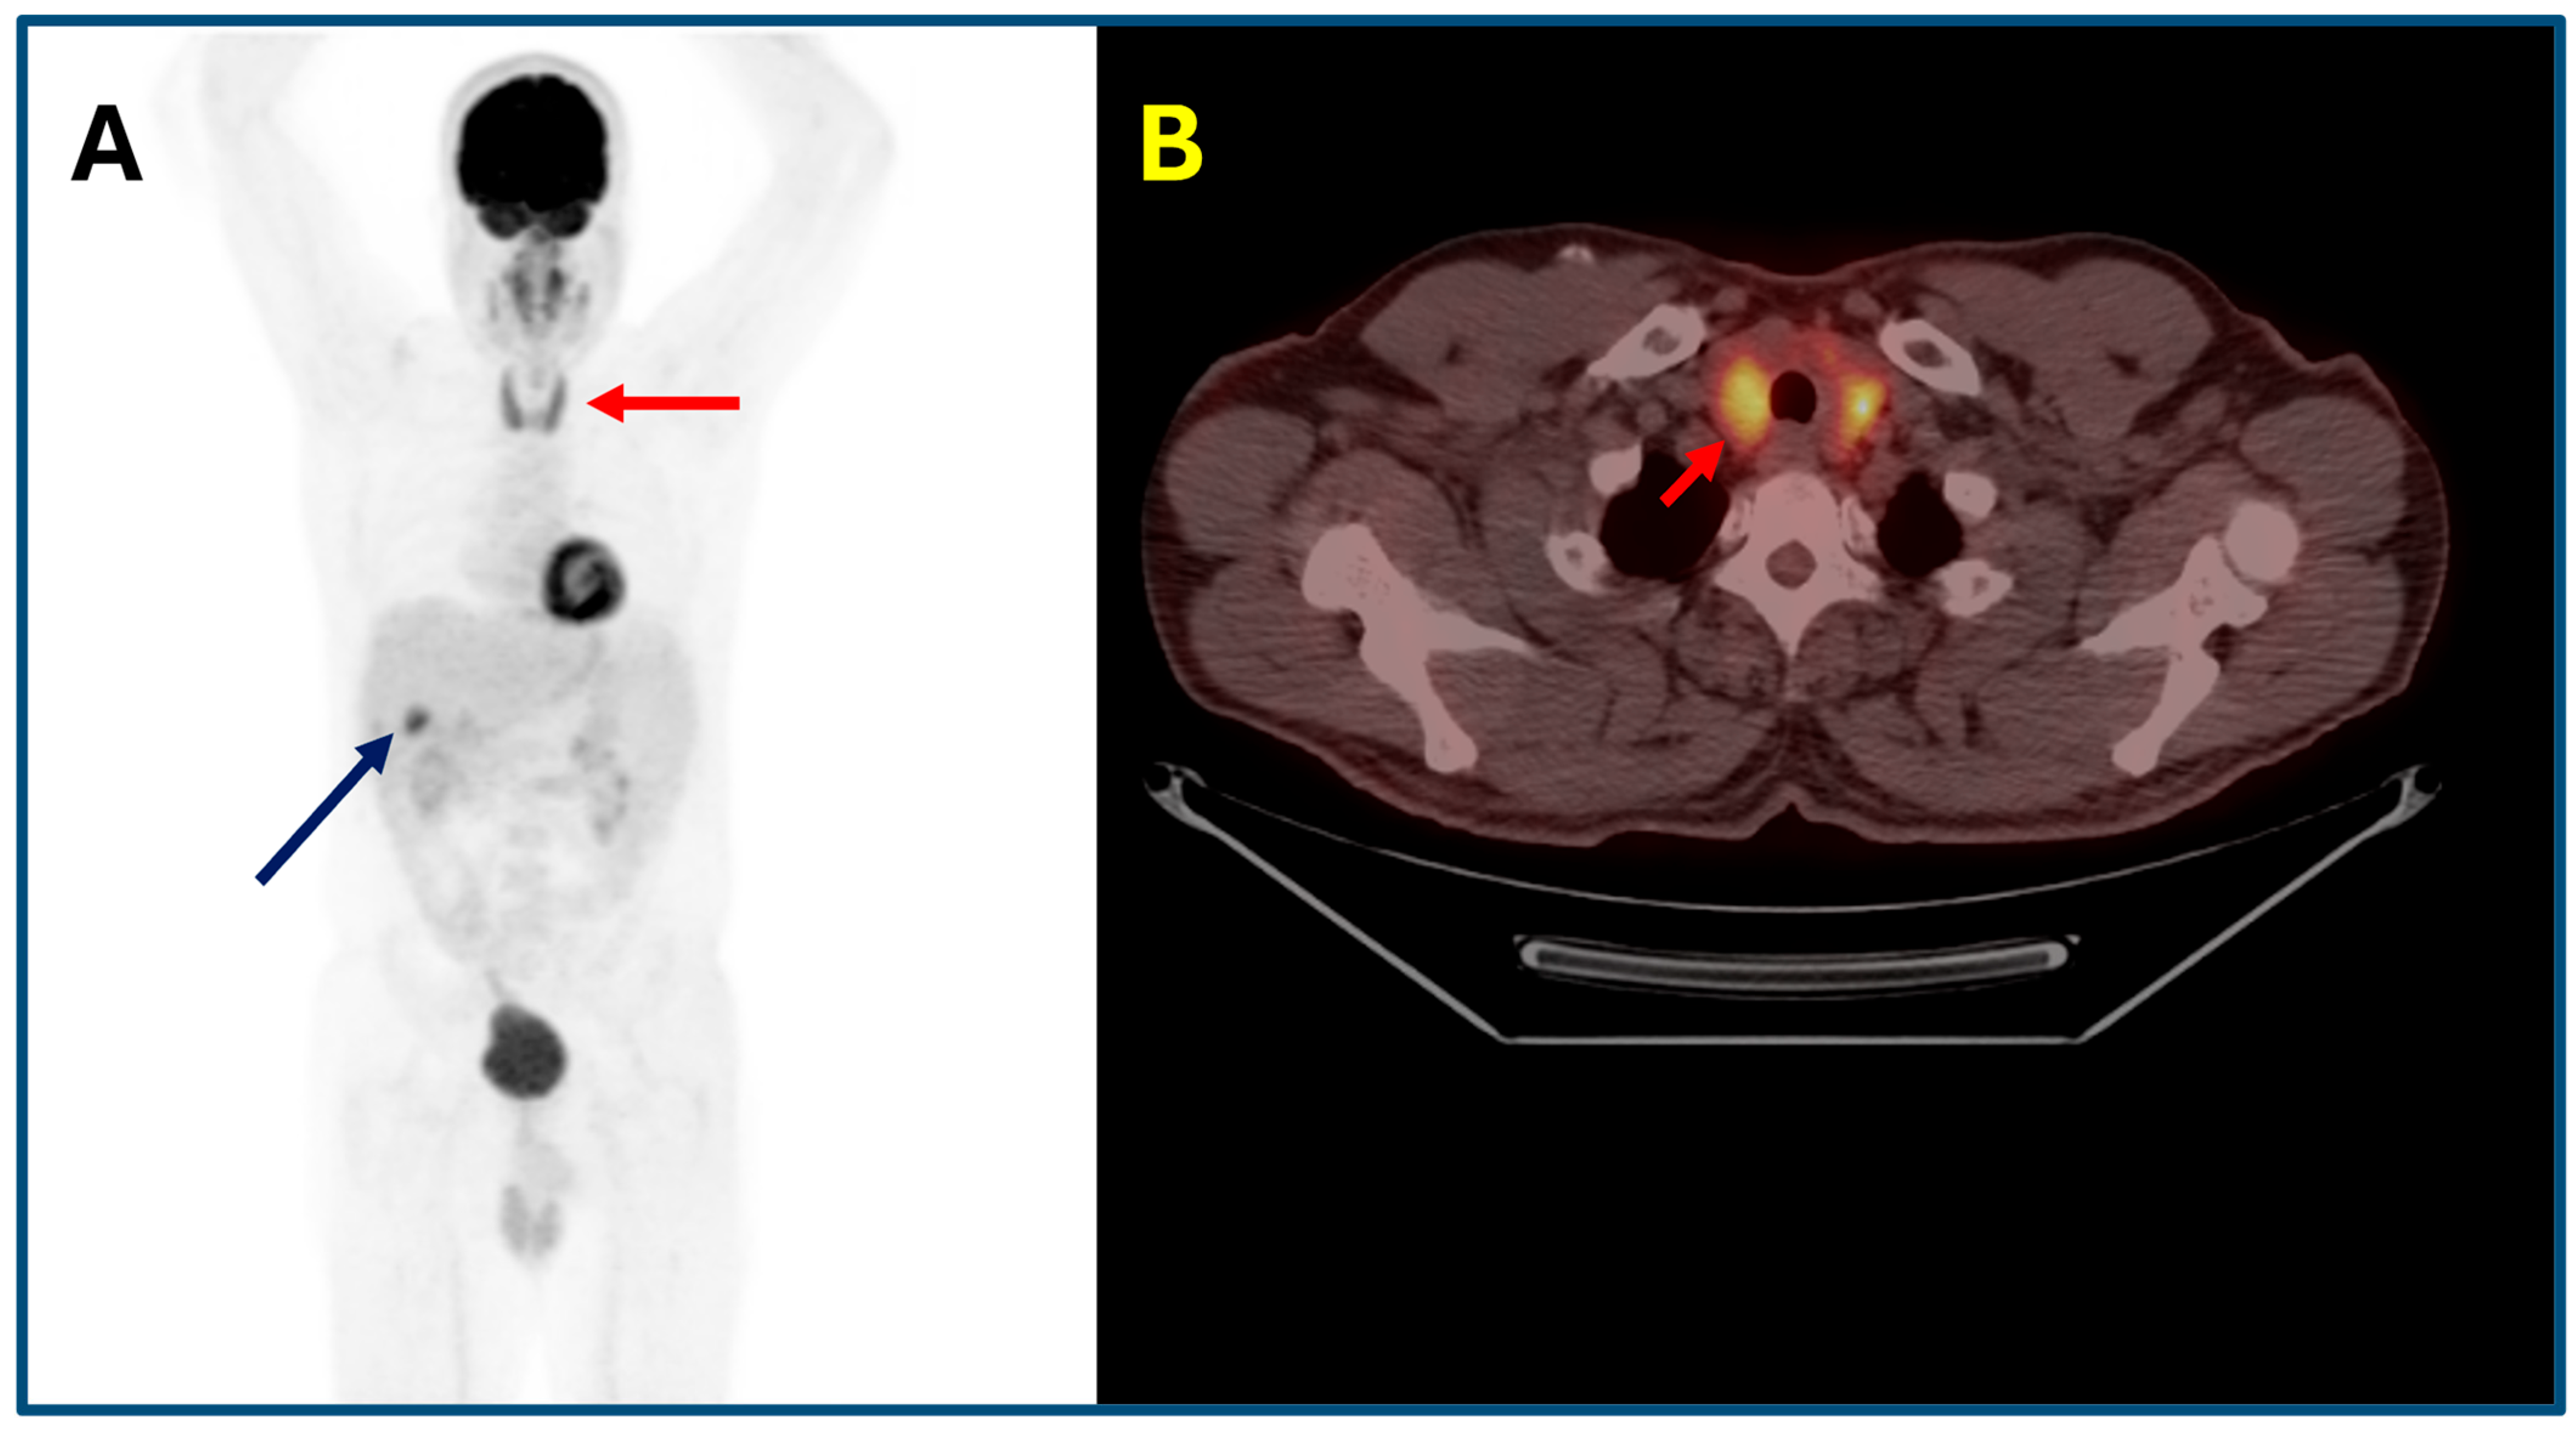

Figure 3. A 65-year-old man with melanoma metastatic to abdominal lymph nodes ((A); axial PET/CT fusion images, yellow arrow) underwent a combination of ipilimumab and nivolumab. Following treatment initiation, an 18F-FDG PET/CT scan was performed to assess response. A focal pituitary uptake, highly suspicious for hypophysitis, was detected ((B); axial PET/CT fusion images, red arrow). Although the patient was asymptomatic, biochemical evaluation confirmed panhypopituitarism, and appropriate endocrine therapy was started.